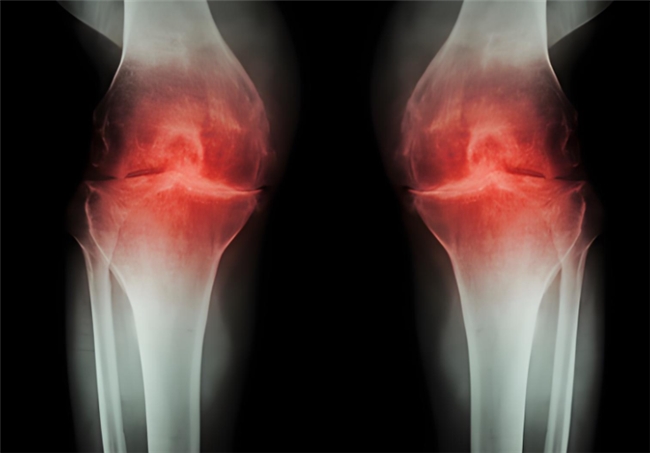

长期高油高糖、饮食不规律,很容易导致体重超标,而肥胖正是关节的 “隐形杀手”。多余的体重会让膝关节、髋关节等负重部位承受巨大压力,加速软骨磨损,久而久之,关节疼痛、僵硬、活动受限等问题接踵而至,大大增加骨关节炎的发病风险。而一旦患上骨关节炎是不可逆的,需要长期管理来延缓病情进展,氨糖就是临床常用,修复软骨、抑制损伤的优选。但它还有两种类型,到底盐酸和硫酸氨基葡萄糖有何不同?骨关节炎患者应该选哪个呢?